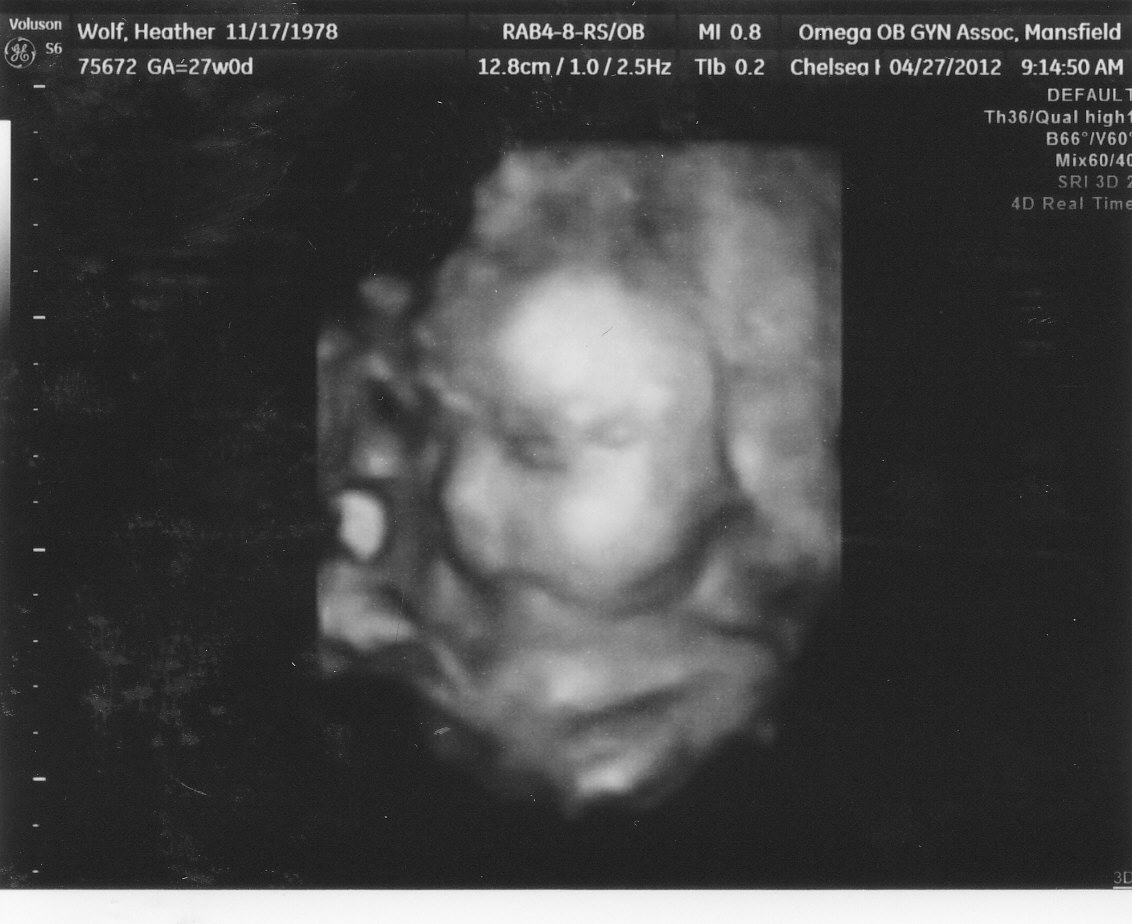

We also got to see some 3D pictures - so amazing! Here are the best two of our two =)

| Thi is our baby girl =) she's looking left and you can see her cute button nose! |